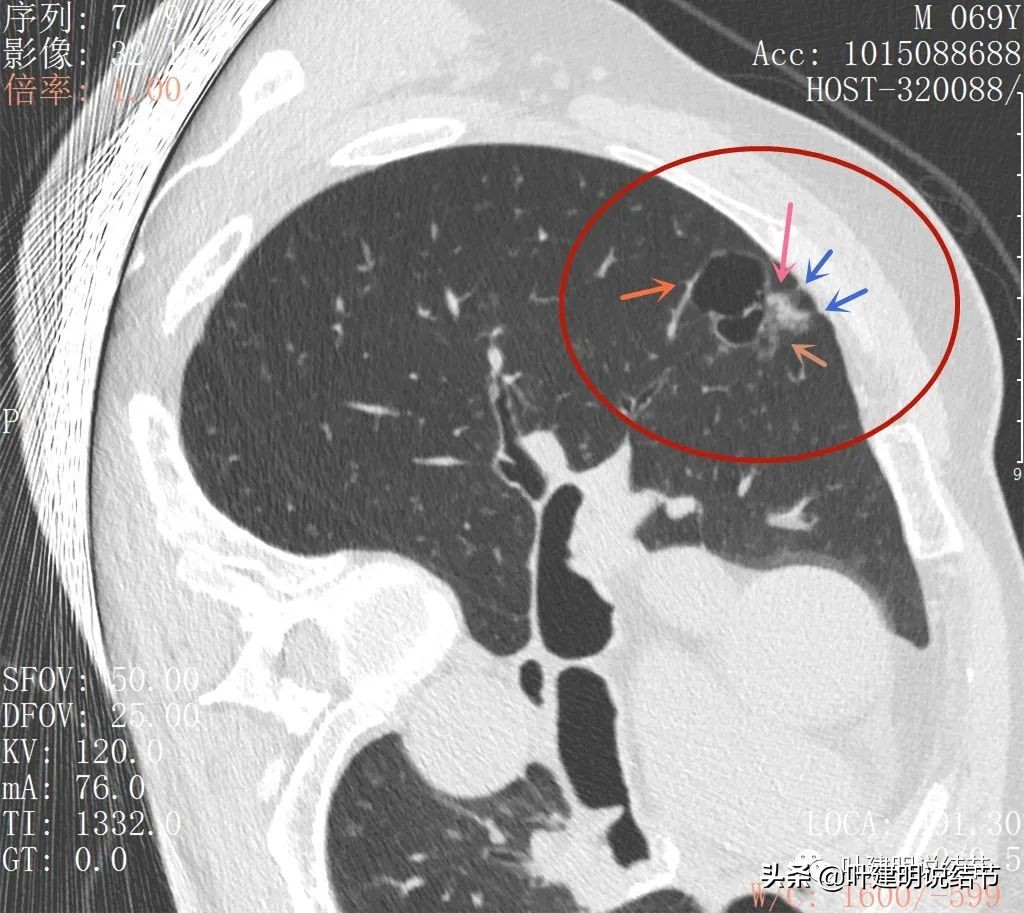

去年11月份,复查了右侧靶扫描,最大层面的主病灶以及对比图如下:

感觉怎么囊壁实性成分密度有点显得高,粉色箭头所示处明显密度不均,偏高密度;蓝色箭头示有胸膜牵拉;砖色箭头示分叶征;桔色箭头示血管走向病灶。我觉得关键是病灶位置好,紧贴胸壁,能局部楔形切除,对肺功能影响小,又能去除危险。倾向切了它!